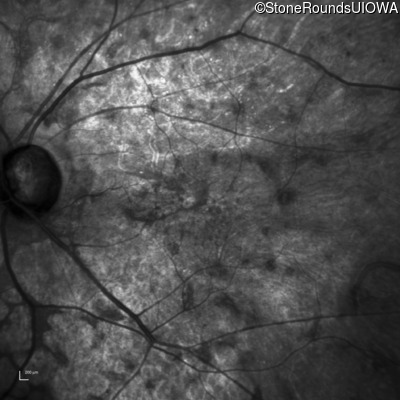

This 81 year old man began using a flashlight to read menus in his 40's. At age 75 his ophthalmologist noticed abnormal fundus findings and referred him to a retina specialist.

| Age at visit: 81 years |

| Age at visit: 82 years |

| Age at visit: 83 years |

| Age at visit: 84 years |

| Age at visit: 85+ (Visit 1) |

| Age at visit: 85+ (Visit 2) |